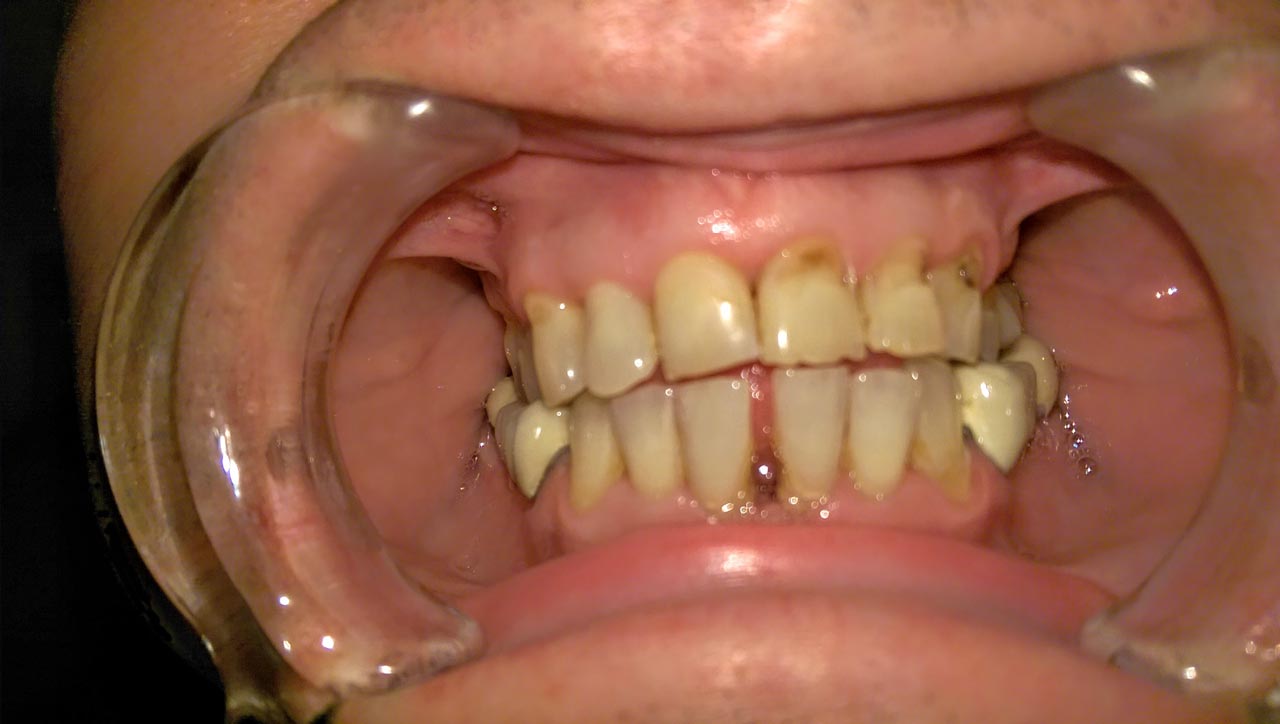

Elhanyagolt fogsor cseréje 2 nap alatt

2 nap alatt varázsoltuk ezt a szép esztétikus alsó, felső körhídat implantátumokkal megtámasztva a korábban elhanyagolt szájba. Az 1. nap 26 fogat távolítottunk el, mert annyira rossz állapotban voltak, és rögtön azonnal terhelhető IHDE svájci implantátumokat raktunk be, fentre 8, lentre 6 darabot. A sebeket összevarrtuk és intraorális szkennerrel digitális lenyomatot vettünk. 2 nap múlva pedig beragasztottuk a kész PMMA műanyag körhidakat. Dr. Kelemen Péter és a Symbion Fogtechnika munkája.